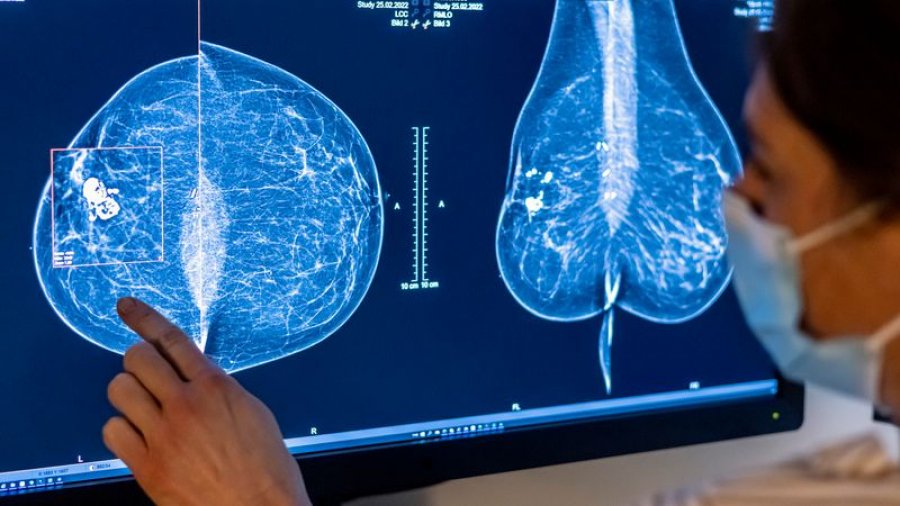

Për vite me radhë, “rregulli i artë” për depistimin e kancerit të gjirit në shumë vende, ishte të fillohej në moshën 50 vjeç. Por nëse jeni një grua në të 40-at, depistimet tani mund të jenë të disponueshme – dhe të rekomanduara – për ju më herët se më parë.

Meqenëse hulumtimet në disa vende kanë treguar një incidencë në rritje të kancerit të gjirit tek gratë e reja, një numër gjithnjë e në rritje i autoriteteve shëndetësore kanë ulur moshën e rekomanduar për kontrolle.

Përmirësimet në mamografinë digjitale dhe mbikëqyrjen në distancë të “telemjekësisë” nënkuptojnë që skanimet me cilësi të lartë tani mund të ofrohen në mënyrë më fleksibile, duke përfshirë edhe përmes klinikave mobile (autobusë mamografie) që nuk kërkojnë gjithmonë praninë fizike të një mjeku.

Zyrtarët gjermanë të shëndetësisë që mbikëqyrin sigurinë nga rrezatimi njoftuan në mars se ekzaminimet me mamografi tani janë të justifikuara nga ana mjekësore për gratë duke filluar nga mosha 45 vjeç.